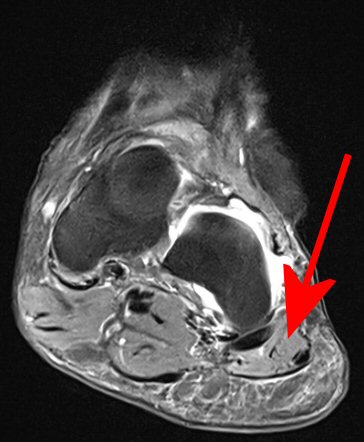

Klinisk diagnos, vid behov MR som visar atrofi av m. abduktor digiti minimi.